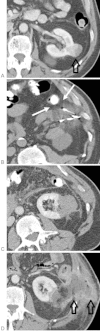

Although percutaneous ablation of small renal masses is generally safe, interventional radiologists should be aware of the various complications that may arise from the procedure. Renal hemorrhage is the most common significant complication. Additional less common but serious complications include injury to or stenosis of the ureter or ureteropelvic junction, infection/abscess, sensory or motor nerve injury, pneumothorax, needle tract seeding, and skin burn. Most complications may be treated conservatively or with minimal therapy. Several techniques are available to minimize the risk of these complications, and patients should be appropriately monitored for early detection of complications. In the event of a serious complication, prompt treatment should be provided. This article reviews the most common and most important complications associated with percutaneous ablation of small renal masses.